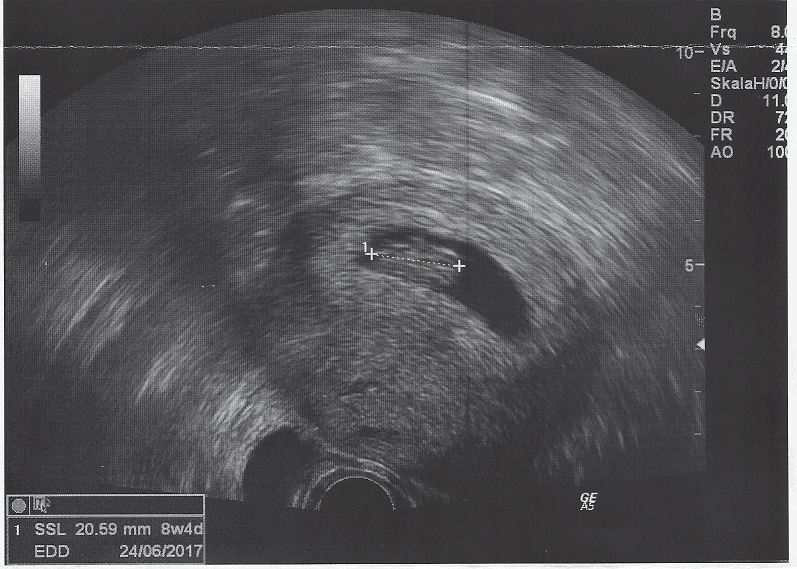

Bardzo mi przykroCześć dziewczyny, dziękuje wam za kciuki ale niestety już po wszystkim... zarodki się zagnieździły, ale nie rozwijają sięSzczerze mówiąc nie brałam takiej opcji pod uwagę, no nic swoje już wypłakałam w sobotę jak spadła po raz pierwszy. Teraz przyjęłam to z pokorą, w poniedziałek mamy zrobić kariotypy, a następna próba za dwa lub trzy miesiące, ponieważ nie mamy niestety zamrożonych zarodków. W programie mamy trzy próby, więc tak szybko się nie poddamy. A teraz planujemy jakiś wyjazd, byle zmienić otoczenie i trzeba wracać do pracy, jakby się nic nie wydarzyło... pozdrawiam was wszystkie ! Mam nadzieję, że będziecie miały więcej szczęścia !